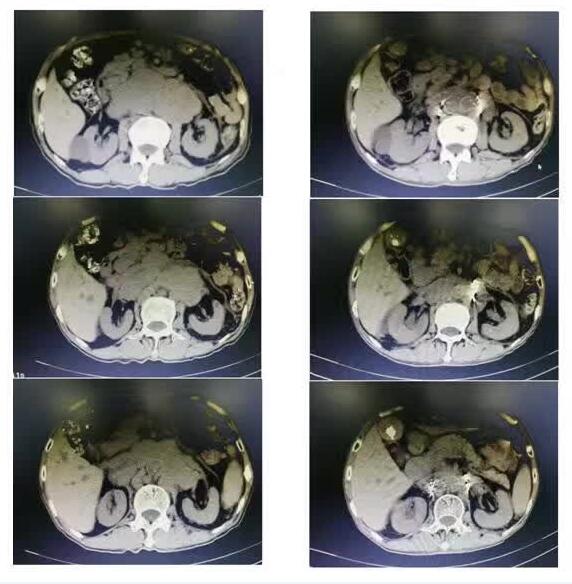

治療前                                治療后

9月8日,劉建民主任帶領(lǐng)腫瘤一科微創(chuàng)團(tuán)隊(duì)為李爺爺做了在CT引導(dǎo)下腹膜后、髂血管旁腫大淋巴結(jié)放射性粒子植入術(shù),1小時(shí)后,手術(shù)順利結(jié)束。大約1周后,李爺爺感身體較前可直立,腹部緊繃感較前松弛,約半月后,李爺爺在不服用止痛藥物的情況下完全感覺不到腹痛,停滯了1個(gè)多月的乒乓球活動(dòng)已恢復(fù)如常,消失殆盡的精氣神又恢復(fù)如初,肚子不痛了自然心情好了,食欲也好起來(lái)了。上月初,李爺爺來(lái)我科復(fù)查,腹部CT顯示腹膜后腫大淋巴結(jié)較前縮小,李爺爺向我科團(tuán)隊(duì)豎起了大拇指,連聲說到:劉主任帶領(lǐng)的團(tuán)隊(duì)真棒,小小的粒子讓癌癥病人也能輕松地活著,且不用服用止痛藥,感謝你們!